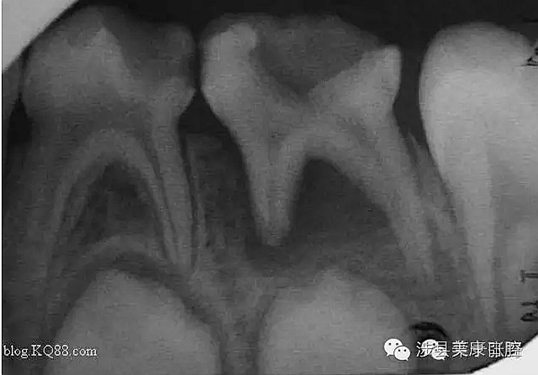

普通家長(zhǎng)看了這張牙片估計(jì)能看出來(lái)孩子的牙不好,但是究竟不好到什么程度呢,讓葉子姐告訴大家:

上圖孩子的乳牙感染已經(jīng)將下面骨感染到吸收消失,并且直接影響到了下面的恒牙胚,家長(zhǎng)們上點(diǎn)心吧。那些說(shuō)乳牙不用治療,換牙就會(huì)好的人(包括醫(yī)生)還是睜開眼睛看看吧,不要自欺欺人,更不要用自己的錯(cuò)誤誤導(dǎo)他人誤導(dǎo)大眾。

網(wǎng)友又不明白了,什么叫吸收消失?看x片看不懂哎......

黑色部分表示那里的骨頭感染已經(jīng)爛沒(méi)有了,消失了,牙胚應(yīng)該在健康頜骨里孕育生長(zhǎng)發(fā)育,現(xiàn)在在感染的病灶里生長(zhǎng),在膿水里侵泡。